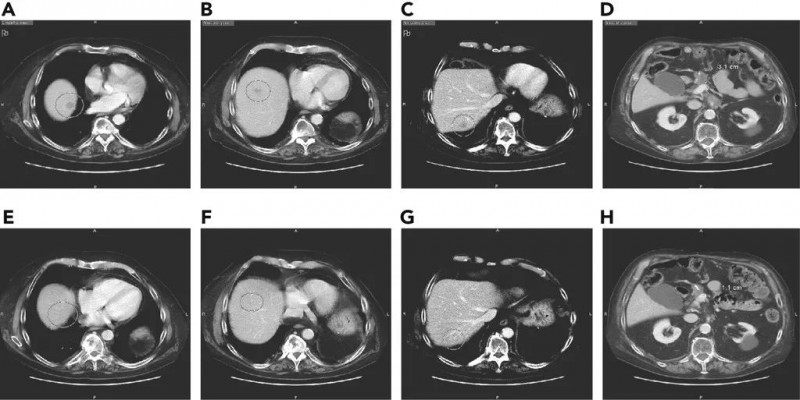

Claudin18.2 CART疗法CT041治疗胰腺癌肿瘤病灶完全消失或大幅缓解肿瘤病灶完全消失或大幅缓解,CT041挑战胰腺癌效果惊艳2023年9月21日,科济药业宣布该公司自主研发的靶向Claudin18.2的CAR-T细胞CT041治疗转移性胰腺癌的两个病例报告已发布在9月9日的《血液学与肿瘤学杂志》期刊上。值得一提的是,这两则典型病例很具有代表性,